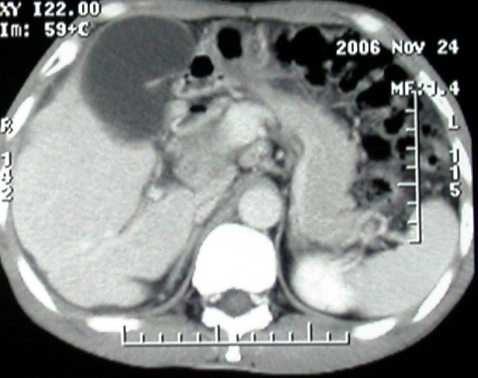

平扫

增强ct所见【动脉增强期】